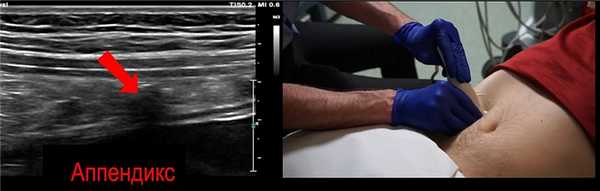

Мы нашили небольшую трубчатую структуру. Это и есть аппендикс

Для лучшего контроля вращайте датчик двумя руками

Полезный анатомический ориентир - поясничная мышца. Аппендикс часто можно увидеть над поясничной мышцей